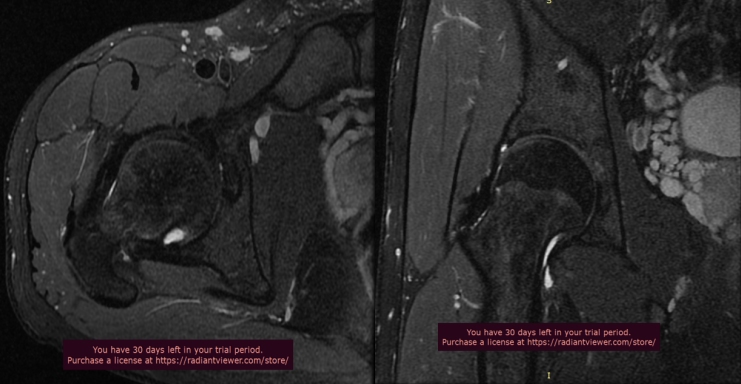

单髋关节一般采用小扫描视野,可以获得更好的信噪比及更高的空间分辨率图像,以及特殊扫描方位(斜冠状位、斜轴位),不但可以显示股骨头颈部病变情况,而且有利于髋臼及臼唇的显示。

下图为我科室扫描单髋关节图

单髋关节扫描对于诊断盂唇损伤和髋关节撞击综合征有非常重要的价值。临床医师如果考虑上述两种疾病,建议开单时选择单髋关节磁共振检查(高分辨率单髋关节扫描),扫描前请电话预约,窗口工作人员会告知您检查注意事项。